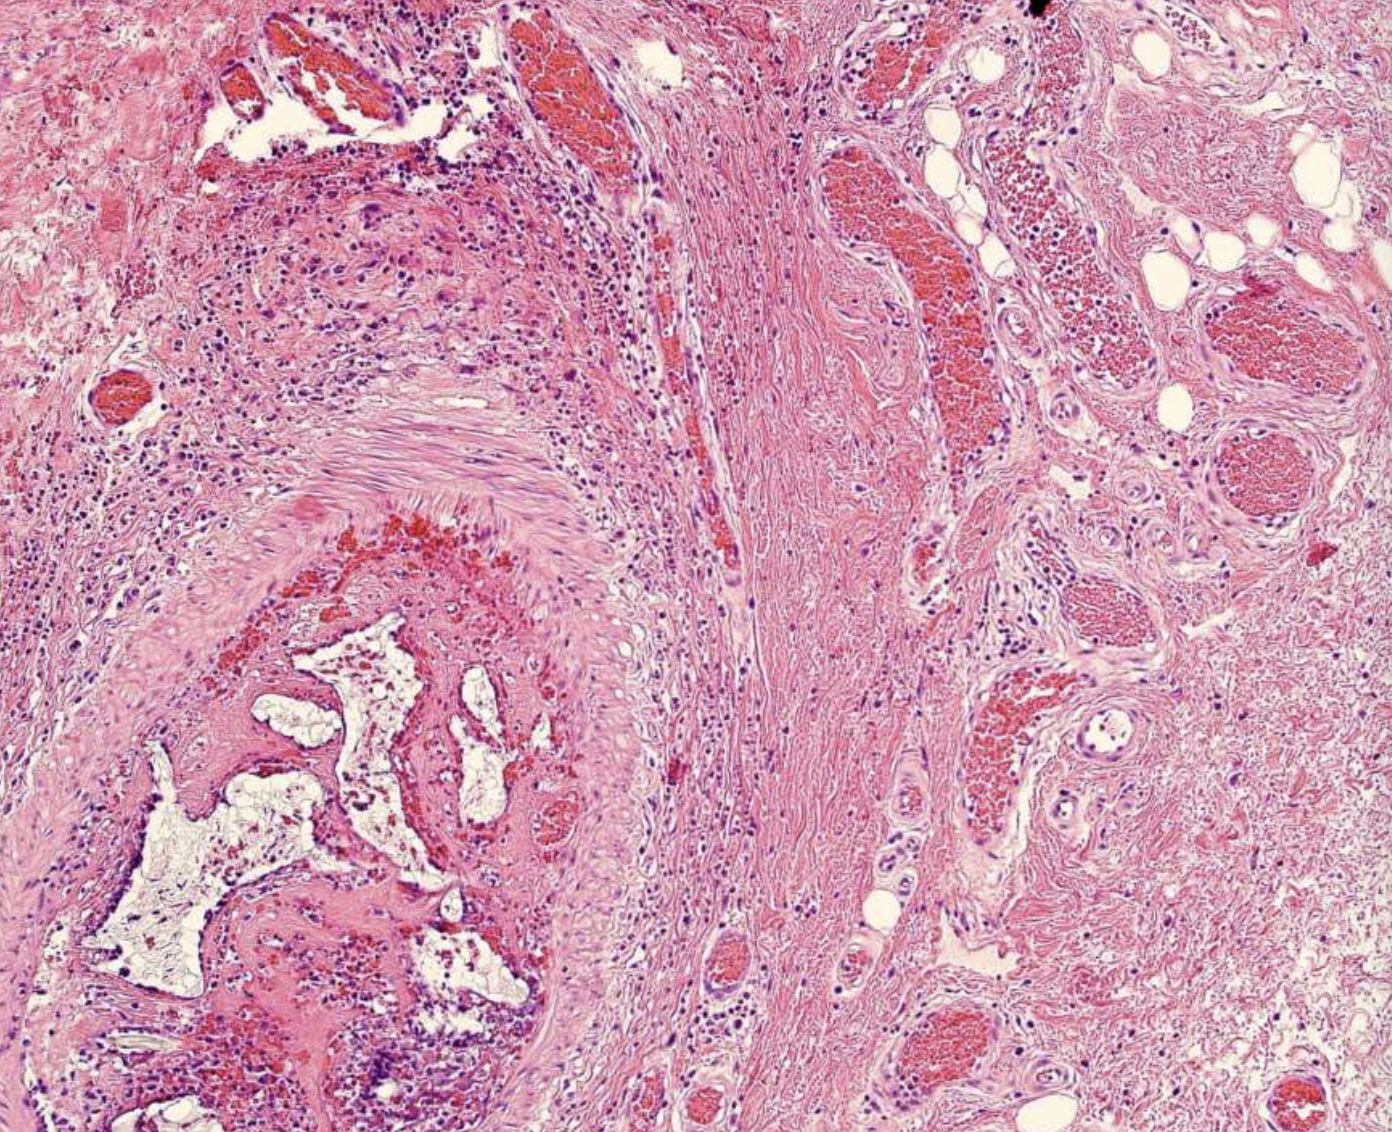

what are the key microscopic histopathologic appearance of ameloblastomas?

Follicular pattern

Nests of epithelium

Island centers resembling stellate reticulum

Peripheral columnar cells with nuclei polarized opposite basement membrane (sub-nuclear vacuolization)

Mature fibrous background

Desmoplastic pattern

Compressed islands and cords of odontogenic epithelium in densely collagenized stroma

ameloblastoma (Island centers resembling stellate reticulum)